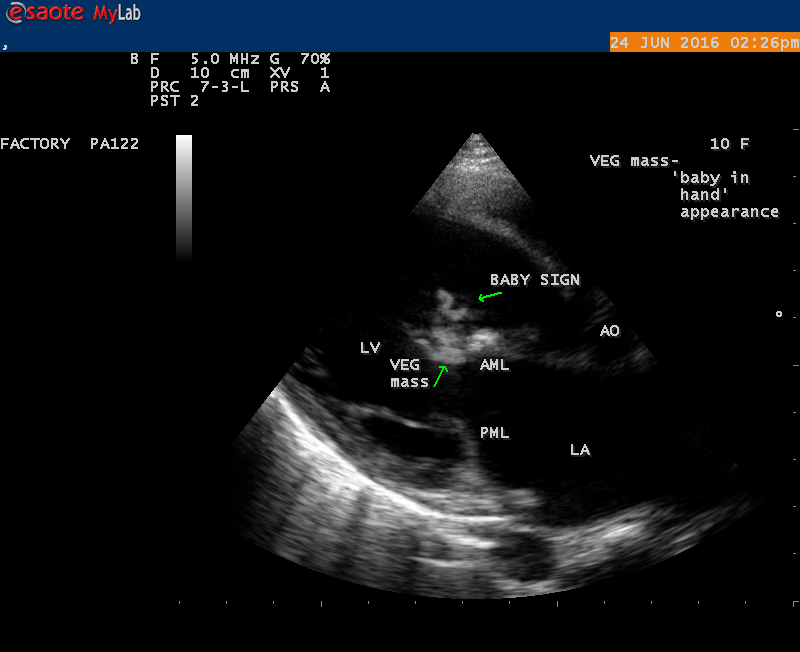

The most common and direct evidence of infective endocarditis is the vegetation and it begins as a microscopic focus of infection and gradually grows into a conspicuous mass. It is typically an irregularly shaped, highly mobile, echogenic mass attached to the free edge of a valve leaflet ( most commonly at the coaptation line) and tends to develop on the ‘upstream’ side of the valve leaflets ( ie, the ventricular side of aortic valve and the atrial side of mitral and tricuspid valves. They may be seesile or pedunculated, but usually has an oscillating or fluttering motion, a typical feature of most vegetations. Vegetation move with the leaflet in a more chaotic (‘oscillating’) manner and it may prolapse through the valve into the LV (left ventricle) as it opens as shown in Figures 3, 4 and 16 and into LA (left atrium) as it closing (Figure 5 and 6) . The mass of vegetation is typically homogeneous with echogenicity similar to that of the myocardium. The infectious process often alter the valvular structure and function. Extensive involvement of the leaflet may result in chordal rupture, leading to severe regurgitation as shown in Figure 21 . Direct and typical signs of RMCT (ruptured mitral chordate tendineae) were chain-flail or whiplash-like changes and had an incidence of 86.7%, causing severe regurgitation and mitral chordal rupture is the leading cause of flail mitral leaflet[30]. A large vegetation may obstruct the valve orifice as shown in Figure 1 and 2 , sometimes termed as “obstructive-type bacterial endocarditis” and producing a functional valve stenosis ( Ping-Pong mitral stenosis [31]) similar to left atrial myxoma as shown in Figure 29.

The shape and size of vegetation are quite variable and mostly it is polypoid [32]. The typical vegetation is a ‘sessile’ or ‘ pedunculating’ valve – attached mass. A ‘sessile’ vegetation had to be completely attached to the valve as shown in Figures 34 and 35 in a 63- year old male, in which a large vegetation is attached to the atrial side of anterior mitral leaflet [33-Figure 13.3-A], producing severe mitral regurgitation as shown in Figure 36 and a mobile vegetation showed a pedunculating part prolapsing into the ventricle as shown in Figure 3 and 4 or atrium as shown in Figure 5 [33-Figure 13.1] in a 10-year old female child. A vegetation was considered as ‘definite’ when shaggy echoes in the M-mode study as shown in Figure 20 . and a corresponding mass without restricted valve motion in the two-dimensional echocardiogram were found as shown in Figure 16 and 30 [33-Figure 13.7]. The vegetation vary in size, often being just a few mm and sometimes reaching to 2-3 cm. A vegetation must be atleast 3 to 6 mm in size to be reliably seen. The mean size of vegetation was 0.6 mm (range 3 to 28) and vegetation > 10 mm in diameter was defined as ‘large’ and those ≤ 10 mm in diameter was defined as ‘small’ and ≥ 15 mm is ‘very large’. Vegetations resulting from fungal infections (candida, aspergillus) are usually much bigger than bacterial vegetations and can be so big to be mistaken for a cardiac tumor. The large vegetations are at increased risk for embolic complications [34], especially on the anterior leaflet of the mitral valve with mobility [35]. A vegetation size of 3.2 x 4.4 cm is called as ‘giant vegetation’ on the mitral valve with a fibrillary appearance of the mass [36- Figure 3] as shown in Figure 1 is an important predictor of embolic phenomena in patients with infective endocarditis causing severe mitral regurgitation as ‘Duck’ shaped jets (Figures 24 and 25 ), disorganized (Figure 21) and sometimes the regurigitant jet splits into two components as one into LA and the second one into LV simultaneously as a bileaflet jets (Figure 10 ) similar to bileaflet structure of AML with vegetation masses (Figure 9 ) . The size of the largest vegetation reported on the mitral valve in the literature in patients with bacterial endocarditis is 7x4 cm[37]. In a study of Nunes, et al[38], vegetation size >13 mm was the only independent predictor of mortality, but some studies [39],[40] did not had an increased embolic risk in patients with vegetation focused only on its presence and size and not on their location. Embolic complications may occur in infective endocarditis(20.6%)and were not more prevalent in the groups with large vegetations [41]. However, Wong, et al [42] found an increased need for surgery in patients with a large vegetation (>10 mm).

The size and shape of vegetation vary due to curling of vegetation. The size of vegetation in this child is 35.6 x 9.3 mm as in Figure 17 , 20 x 23.7 mm as in Figure 1 , 32.9 x 13.9 mm as in Figure 2 .

The shape of vegetation varies in this child as ‘popcorn’ like (Figures 1,3 and 4 ), rod-shaped (Figure ), basket shaped (Figure 7 )[33-Figure 13.3], ‘baby in hand’ appearance (Figure 18), ‘cucumber shaped (Figure 2 ) and a ‘bunch of plantain’appearance (Figure 33 ), ring shaped (Figure 19 }, bileaflet structure (Figure 9 )with bileaflet MR jet as shown in Figure 10 . and kissing forms (Figure 13 - parasternal long axis view, Figure 14 - apical four chamber view and Figure 15 - short axis view)